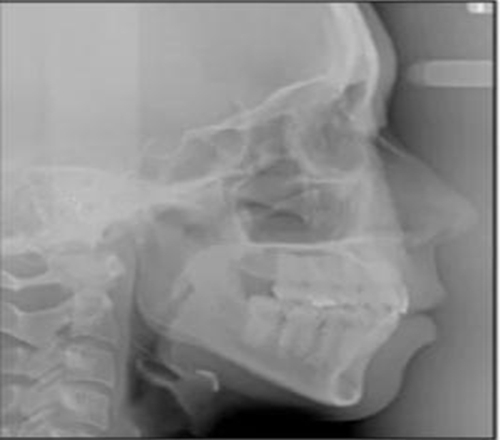

治療后頭側(cè)數(shù)據(jù)提示:無明顯骨性變化(上頜SNA82.1°,下頜SNB74.9°),上頜前牙得到內(nèi)收,略舌傾,頦部前后位置無明顯改變,仍未凸面型(圖8,表)。將治療前后圖像重疊后結(jié)果如(圖8及圖9),24月后隨訪結(jié)果見圖10.